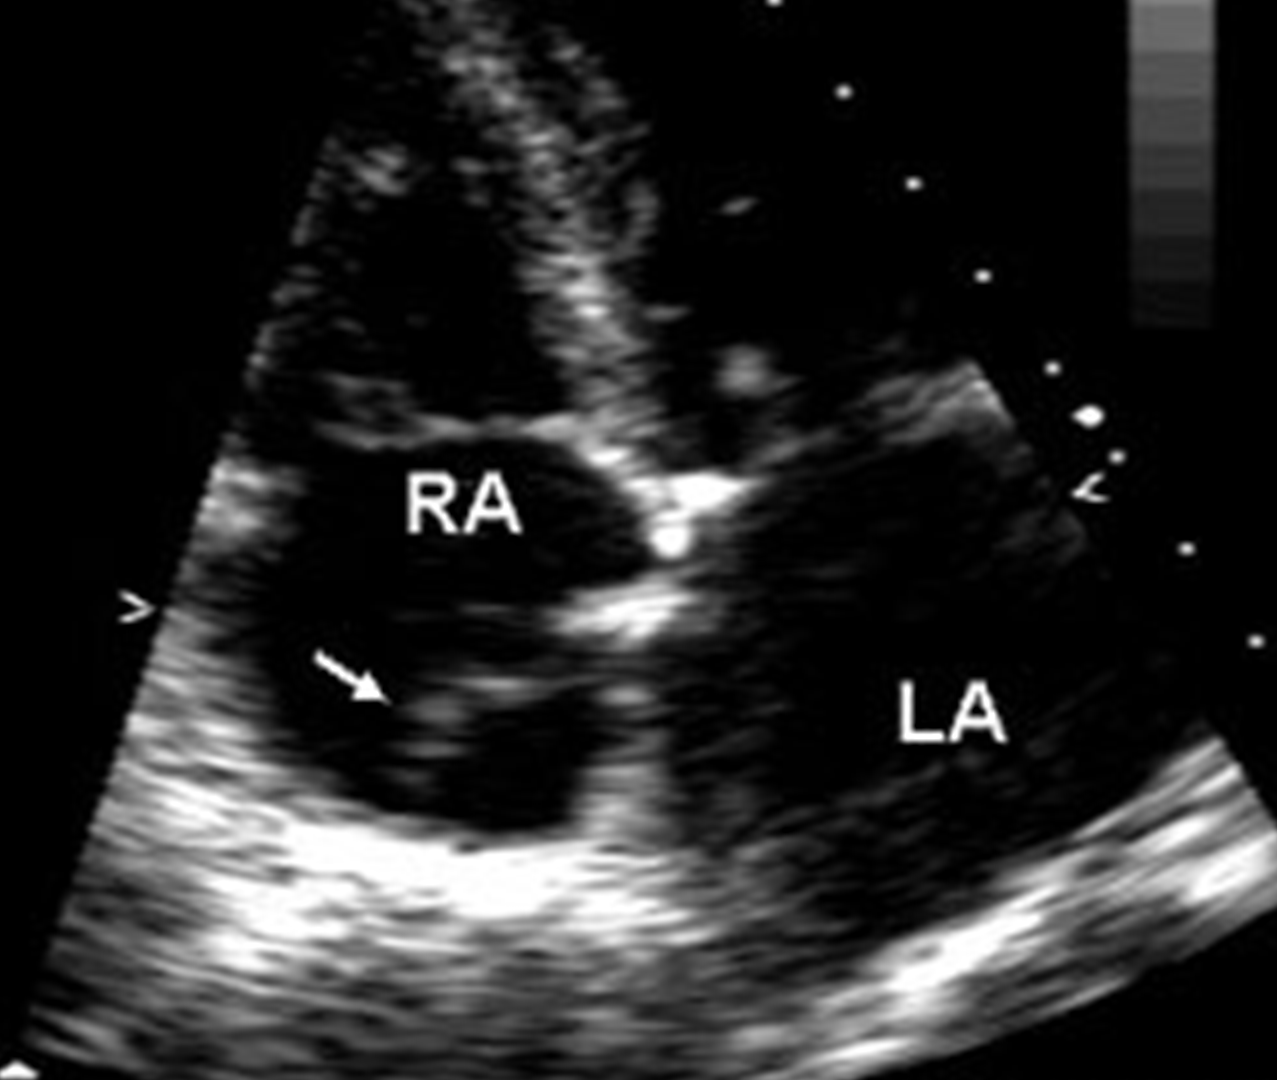

eustachian valve

What are the valves of the heart?

pericardial effusion